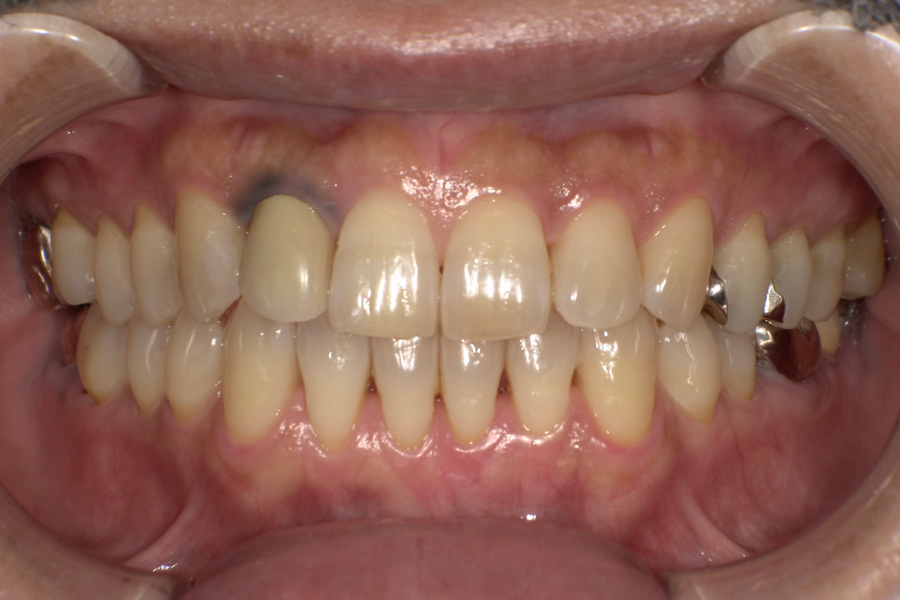

生涯、美味しく食べられる

豊かな人生を

“健口づくり”からサポートする

正しい診査診断、的確な治療をすることで、

歯だけでなく全身の健康に繋がります。

虫歯があるから削ったり悪くなったから抜くのではなく、まずは虫歯と歯周病が起きないようにより良い環境づくりをすること、そうすることによって歯を長く維持することが可能となります。

そのためには、健康状態に関する情報と生活習慣などの状況を把握したうえで、お口の中のリスク評価をおこないます。

その結果をもとに、お一人お一人にあった治療計画をご提案させていただきます。